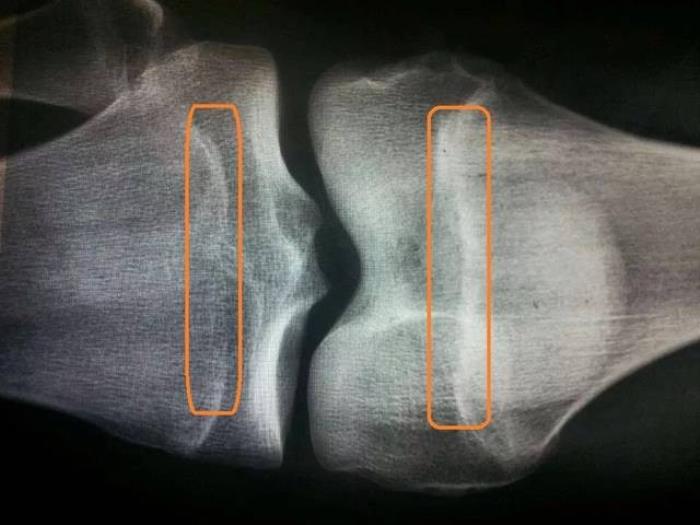

前段时间,一位妈妈带着孩子来医院检查,想咨询一下还有多大的长高的空间,她说孩子13岁多,但是身高才160cm,比同龄人低了不少。拍出来的X光片上显示,孩子的骨骺线相对较薄,快要闭合,在闭合之前身高还有增长的空间,但是能增长多少却因人而异,因为这和以后的饮食、运动、睡眠等都有关系,各方面都做好肯定就能长的高些。

骨骺线是长骨骨干与骨骺之间的一层软骨组织,增长旺盛,能够不断向两侧生成骨细胞,从而使骨骼增长。由于在放射片上类似一条线,而被称为骨骺线。一旦骨骺线出现了闭合现象,就意味着失去了自然长高的潜力。正常情况下,骨骺线会随着年龄的增长而逐渐变薄,骨骺线闭合的时间一般在青春期末尾,但是闭合时间因孩子营养和发育起始时间等因素而存在差异。